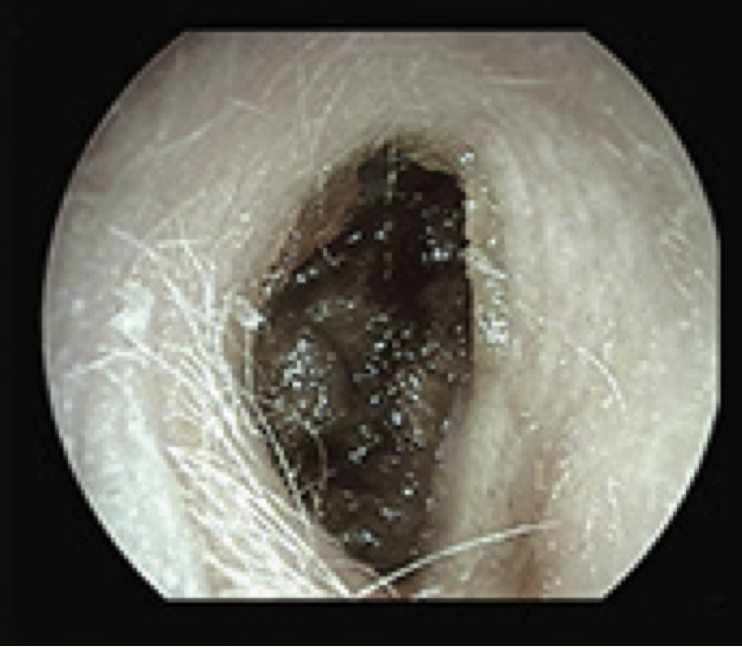

3

Q

What is this?

A

Fungal Ear

- perforated TM

- which fungal hyphae

- yellow spores